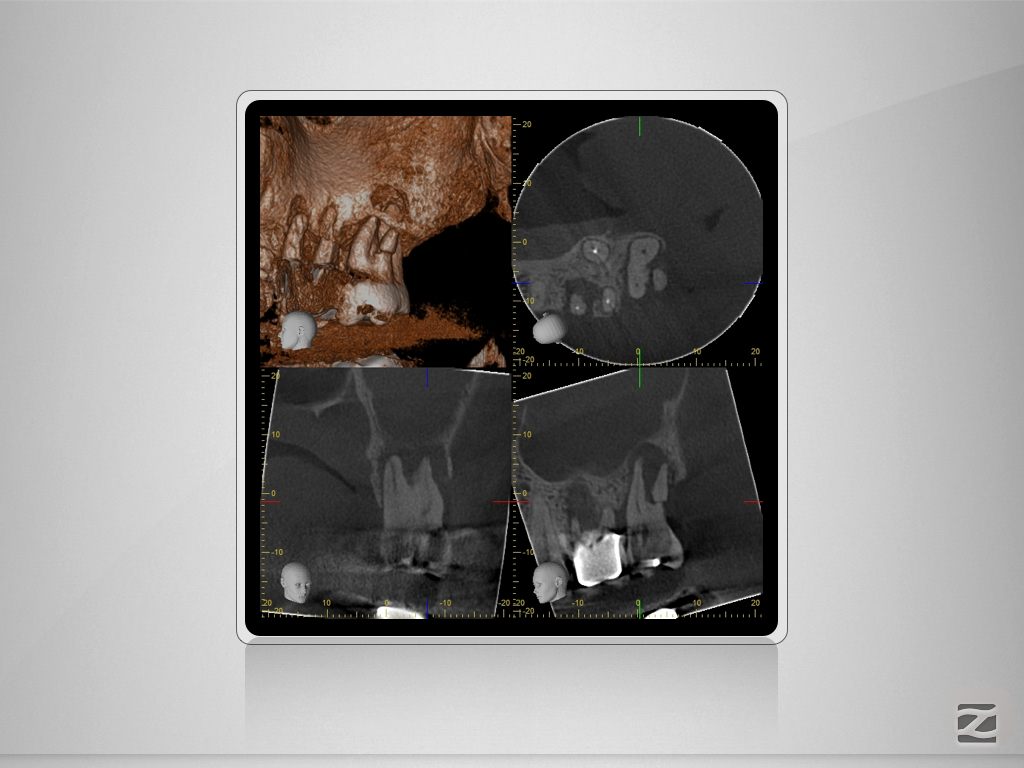

27D.007

Vorher/Nachher – Die Auflösung